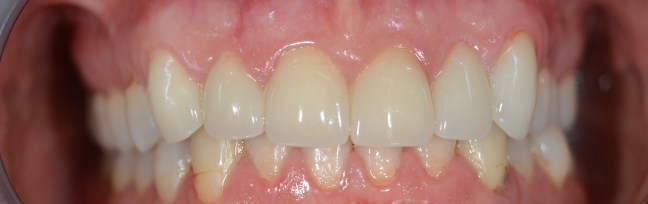

Kozmetikai és funkcionális kezelés: felső torlódott fogak kiegyenesítése, koronák enyhe kifele döntése, mélyharapás korrigálása.

A választott korona típusa: CAD/CAM (komputer vezérelt tervezés/megmunkálás) technológiával készült cirkónium (fémmentes) szóló koronák.

A választott fogszín: A2

A protetikai munka elkészülésének ideje: 5 munkanap.